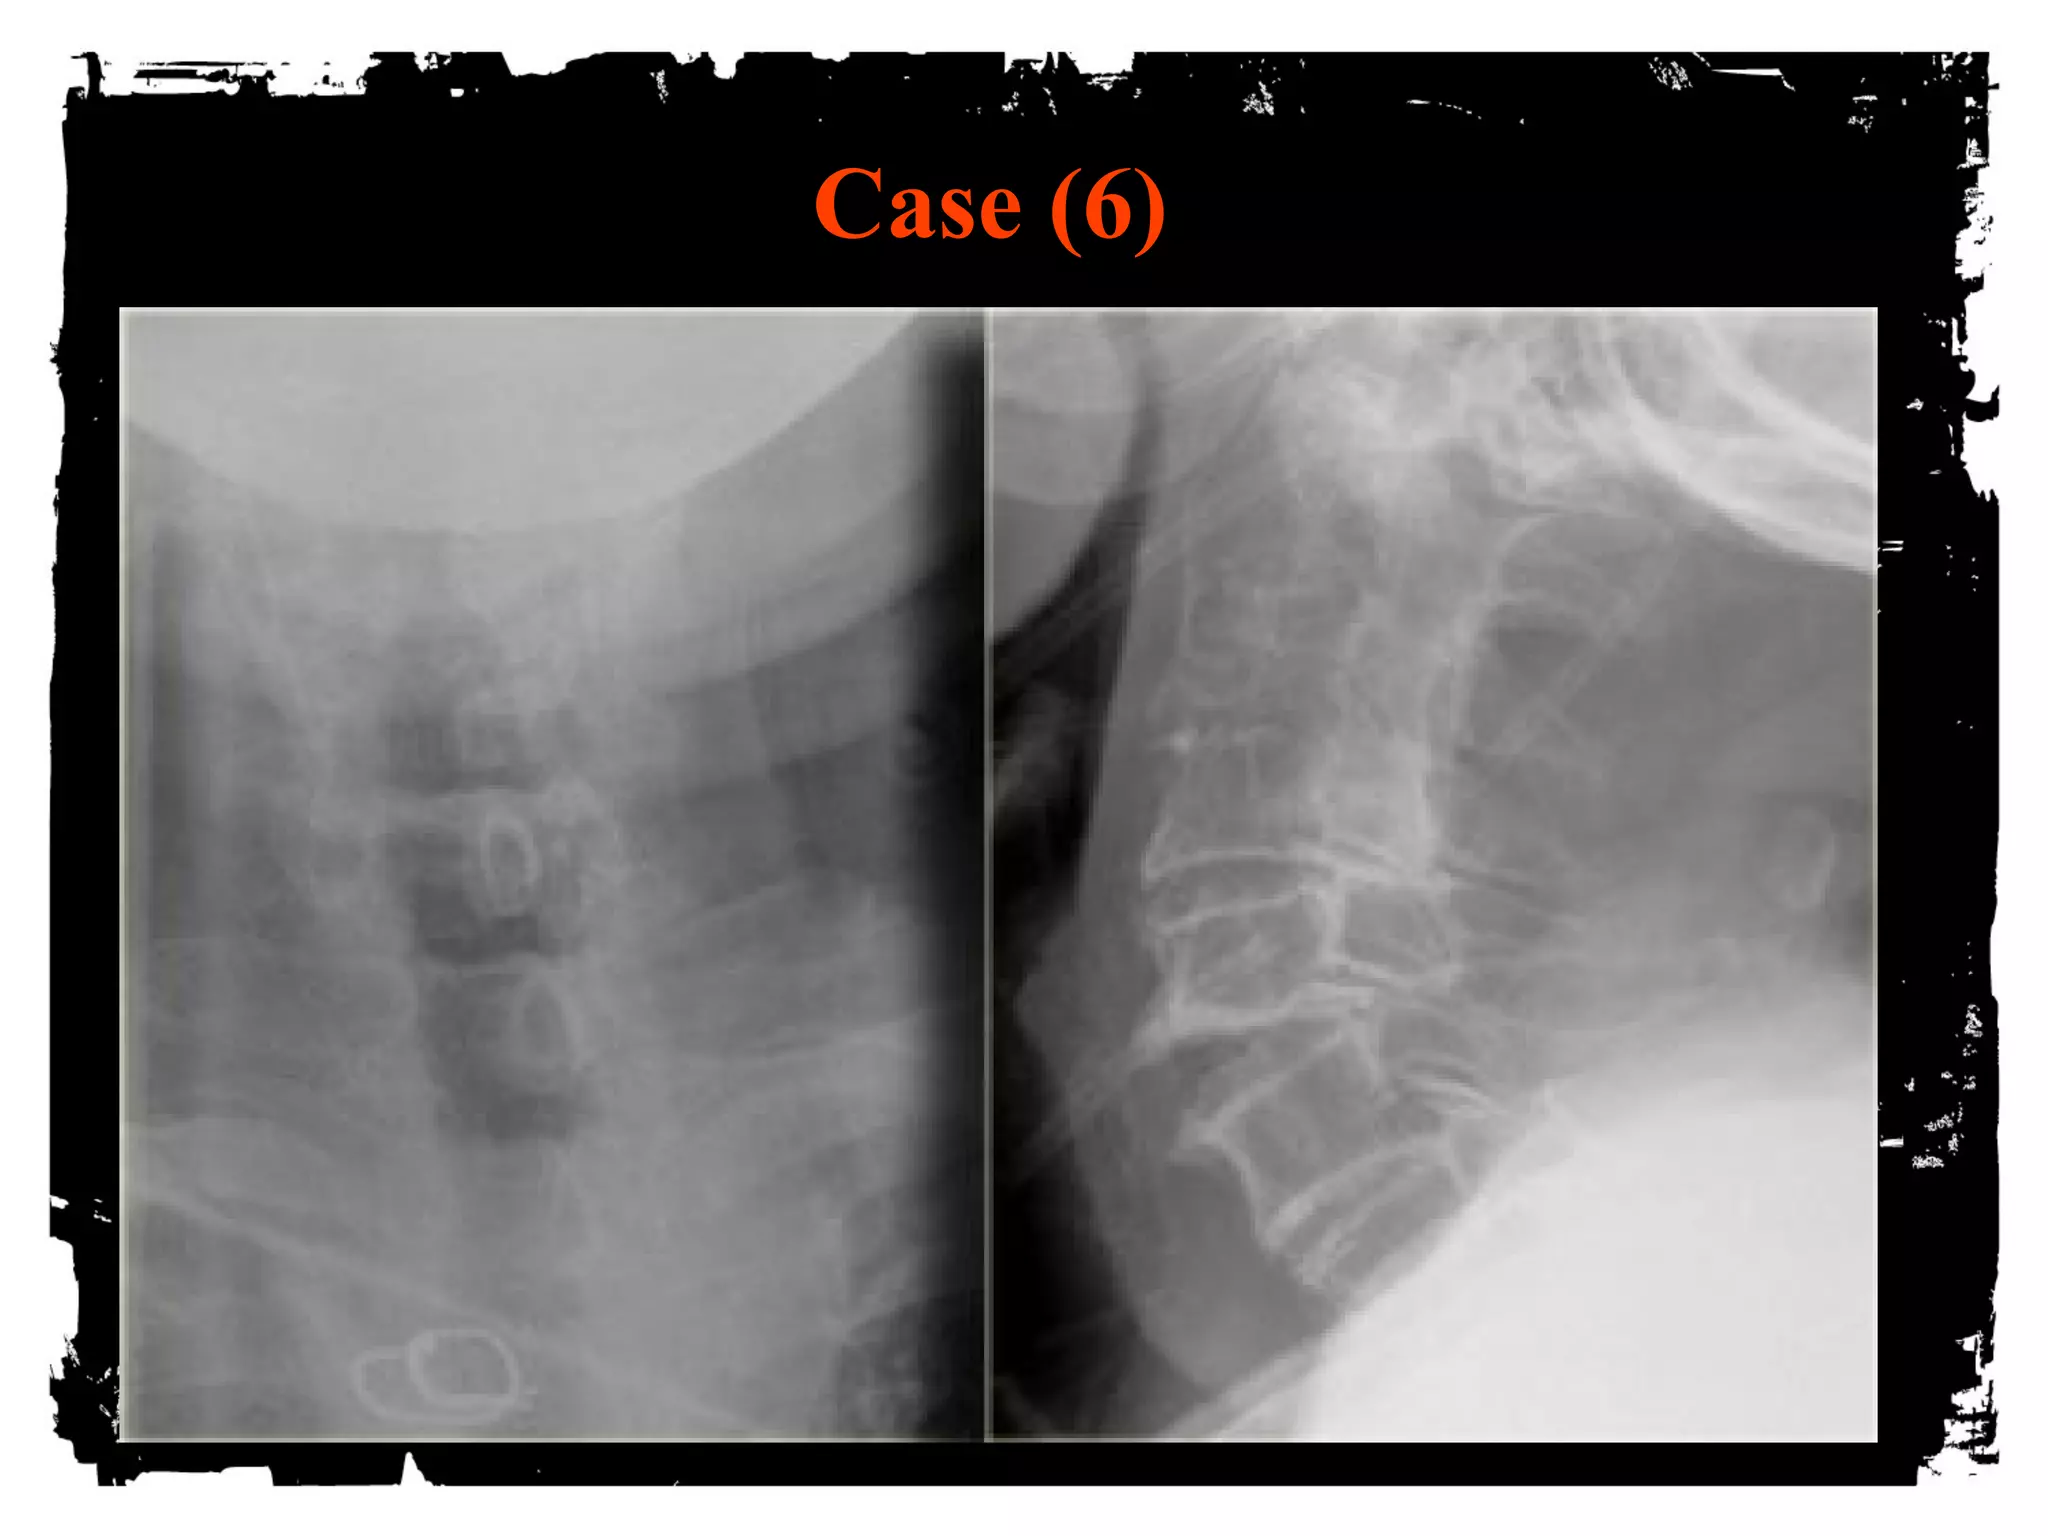

Case (6)

Hyperextension injury

Widening of disk space anteriorly and narrowing

posteriorly

“open book”

Central cord injury= disproportionated weakness in

arms and normal strength in the legs

Injuries can be devastating, however are uncommon

hemorrhagic